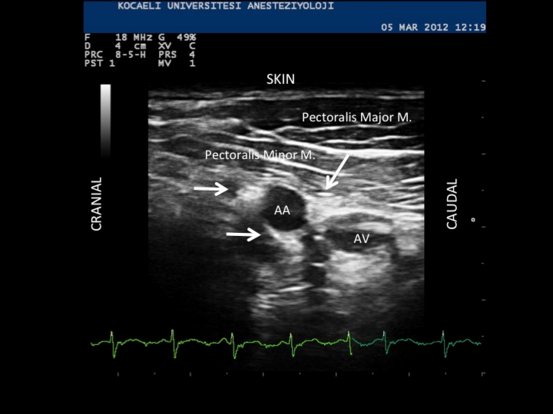

Although LSIB was first performed using nerve stimulation (NS), it is a technique very suitable for US guidance. Important sonoanatomic structures include the axillary artery and three cords of the brachial plexus posterior to the pectoralis minor muscle.[9] Using a linear probe, the prominent pulsatile axillary artery can be easily identified. Brachial plexus cords that surround the artery look hyperechoic and can be identified with high resolution US machines. Yet, sometimes difficulty can be encountered seeing the posterior cord, which lies behind the artery and can be confused with the acoustic enhancement beyond the blood vessel (Fig. 1). Comparative studies have revealed that US guidance further increases the block success rate up to 95%.[10-11] Currently in our clinic, where more than 1000 US guided LSIB has been performed during recent years, our success rate is over 95% (unpublished data). US guidance has also reduced vascular puncture incidence from 20% to almost nil.[6,10,11] In addition to high success rates, improved patient safety, and comfort, US guidance has provided certain advantages that allow the technique to be used in many instances where it would not be clinically feasible with NS alone.[12-14]

Figure 1. AA: Axillary (subclavian) artery, AV: Axillary vein. Cords of the brachial plexus appear hyperechoic. Arrows indicate lateral, posterior and medial cords. The axillary vein can be compressed to some extent.

Some clinicians choose to use both localization modalities, NS and US guidance, simultaneously for the performance of this block. However, avoidance of NS may result in a greater degree of patient comfort, especially in trauma cases, where motor stimulation may be quite painful. In a randomized study, it was shown that during LSIB performance, US guidance alone produces a block success rate identical to the combination of both US and NS guidance, yet provides a shorter block performance time.[16] Block onset time was similar in both groups. The axillary artery is a large, pulsatile landmark that can be easily identified during US scanning (Fig. 1). For these reasons, we recommend using US guidance alone.